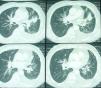

TC torácica (2008): masa de aproximadamente 3cm en LSI. Engrosamientos peribroncovasculares en hilio pulmonar ipsilateral. Adenopatías de tamaño significativo en mediastino e hilio pulmonar contralateral. Derrame pleural izquierdo con engrosamientos nodulares hipercaptantes en pleura de seno costofrénico izquierdo.